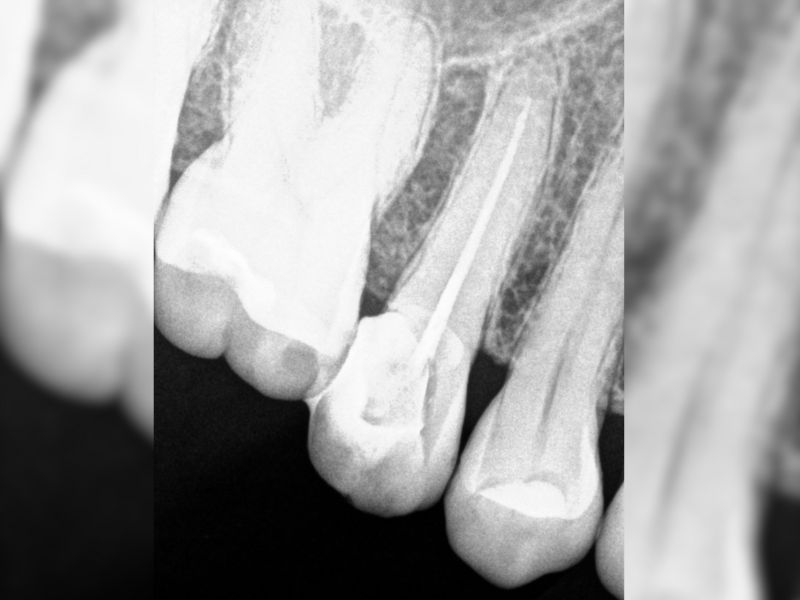

Nuestro Trabajo